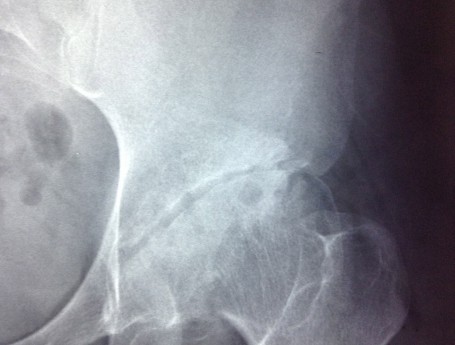

high hip dislocation

• high hip dislocation